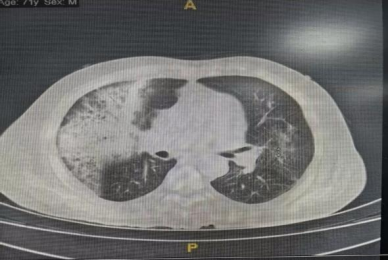

胸部CT:双肺炎症。

11月10日: